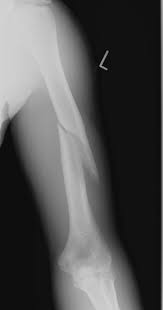

Humerus Mid-Shaft Fracture.

it looks like this...but this isnt my arm.